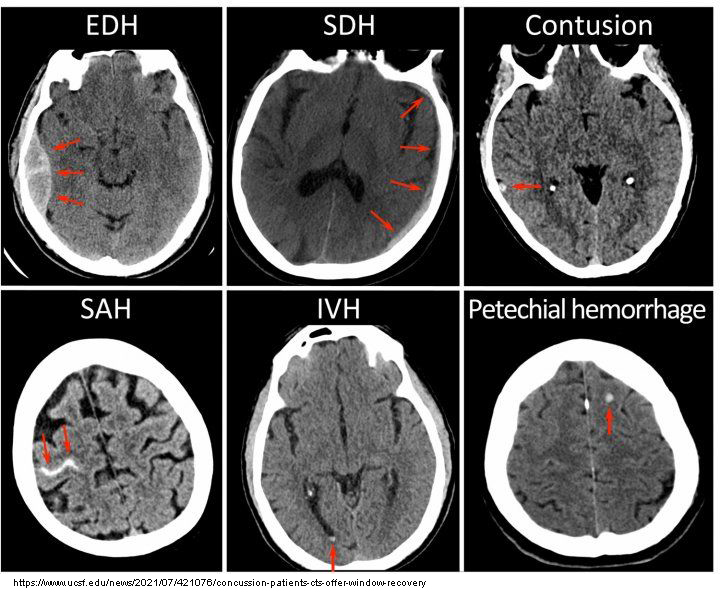

How do fresh cerebral contusions appear on CT?

Hyperdense patches (due to fresh blood).

What is a cerebral hemorrhage?

Bleeding inside the brain; a medical emergency.

What complication can large bleeds cause on CT?

Midline shift of the Falx Cerebri.

What is the difference between arterial and venous cerebral hemorrhages on CT?

Arterial bleeds are faster, larger, and cause more mass effect; venous bleeds may be slower and smaller.